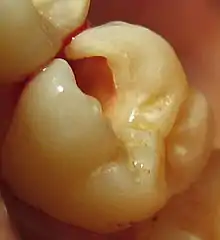

Weakening of tooth structure

In situations where a relatively larger amount of tooth structure has been lost or replaced with a filling material, the overall strength of the tooth may be affected. This significantly increases the risk of the tooth fracturing off in the future when excess force is placed on the tooth, such as trauma or grinding teeth at night, leading to cracked tooth syndrome.